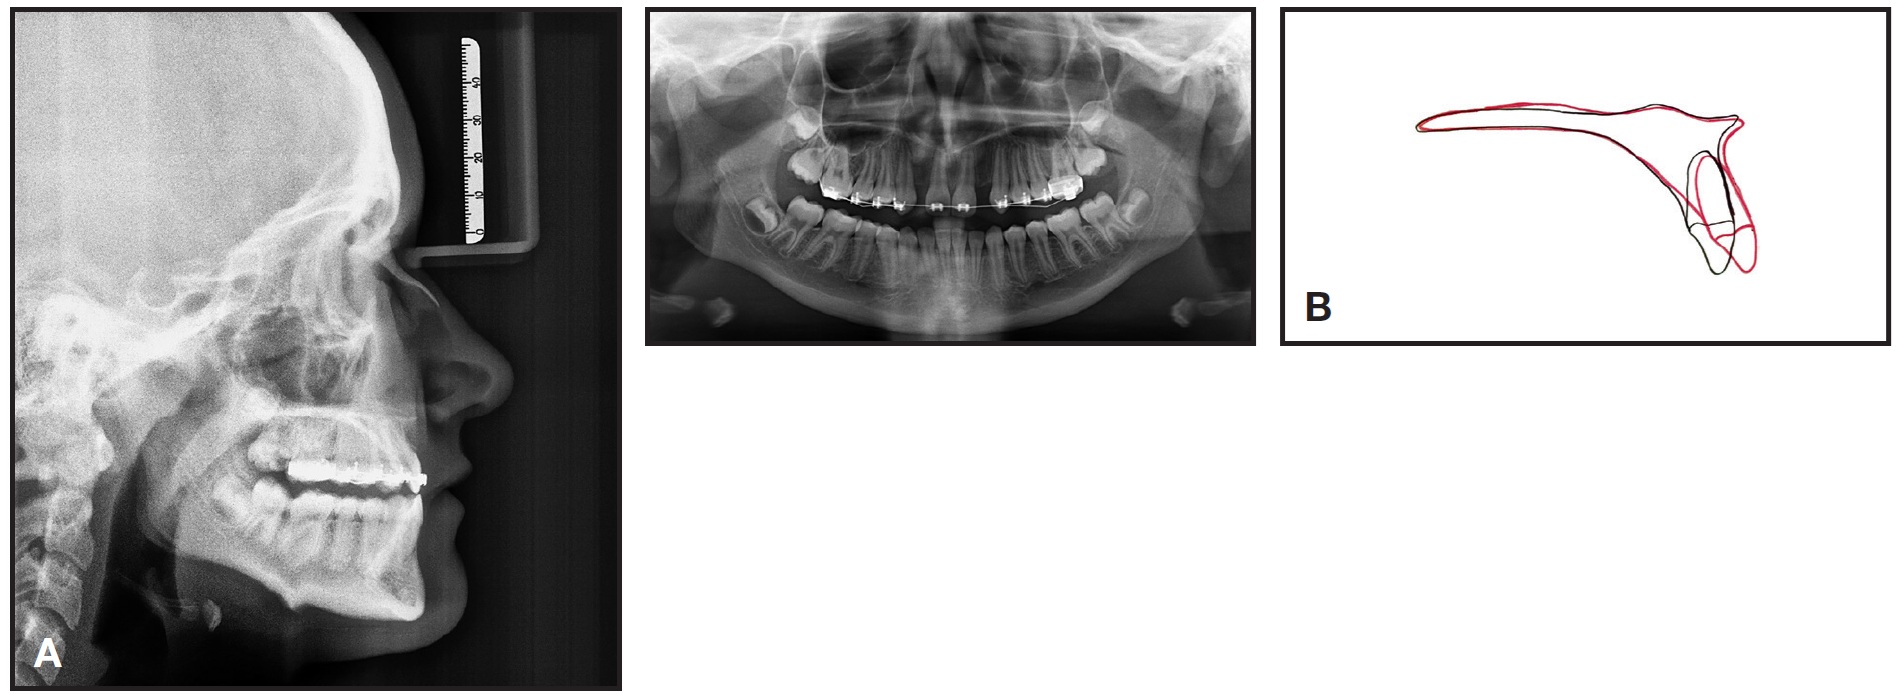

An edge-to-edge bite was achieved in two months (Fig. 3A), and the bite blocks were removed. Cephalometric analysis indicated a 6mm protrusion and some proclination of the upper central incisors (Fig. 3B, Table 1).

Fig. 3 A. Two months after engagement of .016" × .022" TMA* auxiliary advancement arch and micro-osteoperforations. B. Superimposition of cephalometric tracings before treatment and two months after micro-osteoperforations.